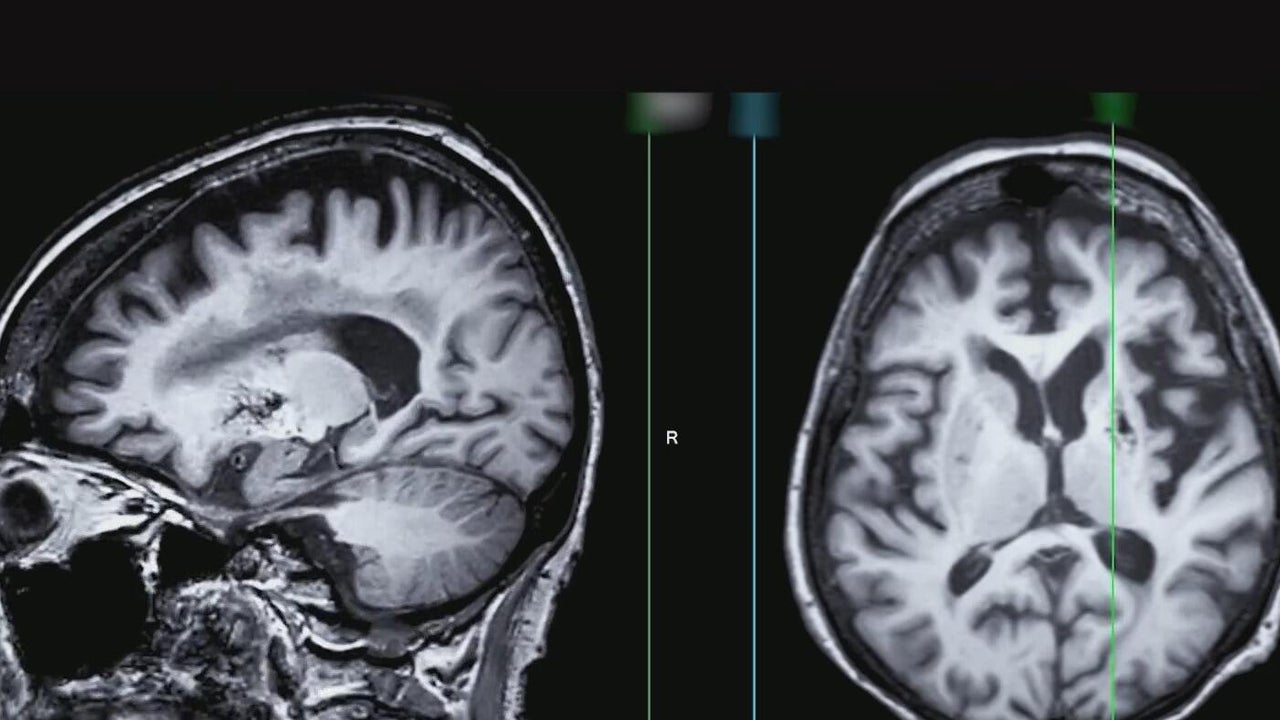

Texas is set to lead the nation in Alzheimer's and Dementia research

Texas is set to lead the nation in Alzheimer's and Dementia research following voters' decision to invest $3 billion in a new research institute.